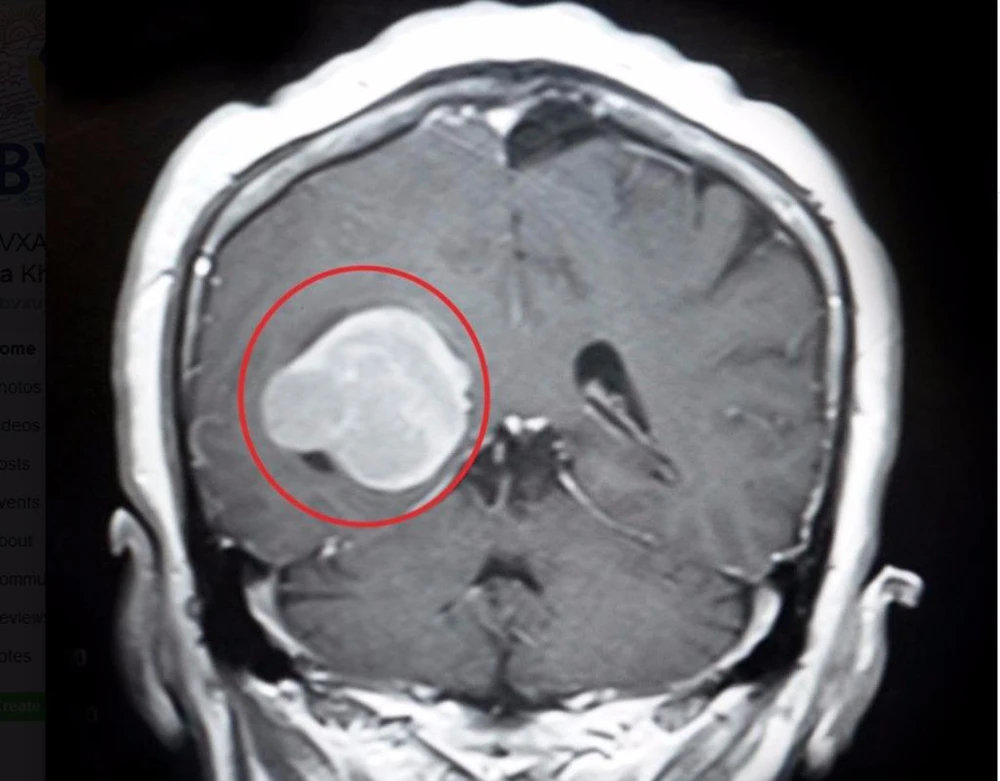

Khối u màng não to như trứng g

Khối u màng não to như trứng gà. Ảnh: LÊ PHỤNG

Các bác sĩ (BS) chuyên khoa Ngoại thần kinh thực hiện chẩn đoán và xác định bà L. có khối u não nằm trong não thất phải, ở vị trí hiếm gặp liên quan tới vùng chức năng vận động và thị giác.

Các BS nhận định một khi u màng não ngày càng to sẽ lấn đè vùng chức năng mô não, làm tăng áp lực nội sọ khiến tình trạng đau đầu ngày càng nhiều. Chưa hết, bà L. có nguy cơ mờ mắt, tay chân yếu dần, rối loạn cảm giác, mất cảm giác da, liệt nửa người. Nếu nặng hơn bà L. sẽ lơ mơ, hôn mê, thậm chí tử vong.